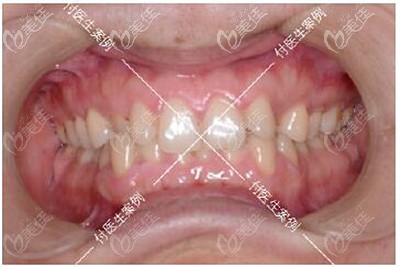

牙齿诊断:牙齿拥挤不齐+深覆合+单颗反颌+下颌方形牙弓

大家可能看我的牙齿图片觉得我的问题不大,但其实我之所以下定决定要去做矫正的原因是因为我的咀嚼功能已经完全受影响了,而且上下牙咬合导致我睡觉经常磨牙、连带着下巴后缩也常常让我觉得自己像“凸嘴”...

深覆合牙齿矫正前后牙齿效果对比